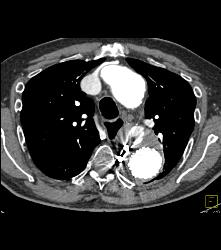

Endovascular Stent With Leak. Also Note Right Axillary Artery Aneurysm